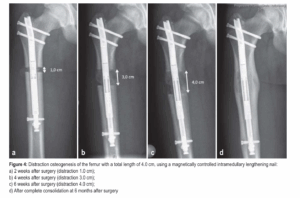

Durante a cirurgia, o osso é cortado (osteotomia) e uma haste motorizada é implantada em seu interior.

Essa haste permite o alongamento gradual e controlado, cerca de 1 mm por dia, sem a necessidade de fixadores externos. Menos dor, mais precisão e recuperação mais confortável.

O ritmo médio é de 1 mm por dia. Por exemplo: para 6 cm de alongamento, são necessários em média 60 dias, seguidos de um período de consolidação óssea até a completa recuperação. Você não pode pisar nesse período se estiver com a haste, mas deve realizar fisioterapia todos os dias.